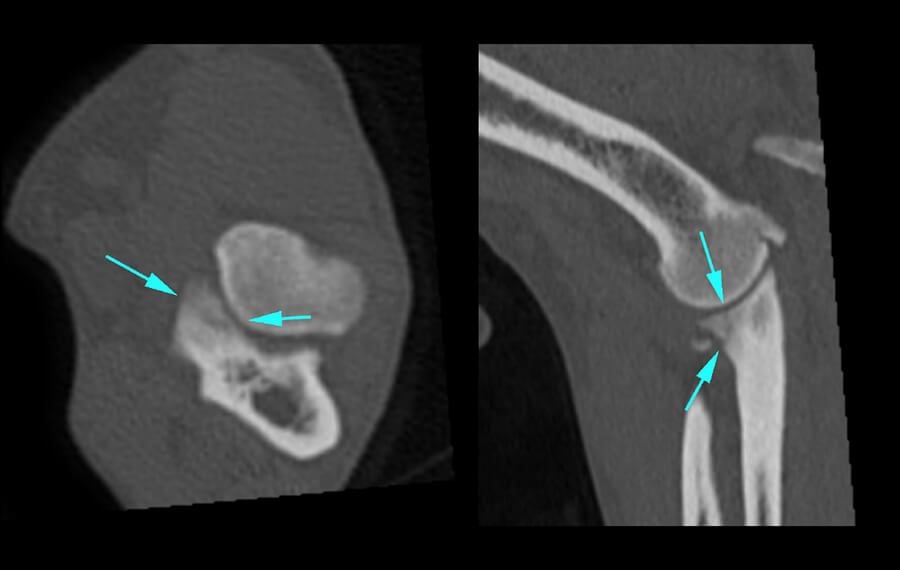

Precision Diagnosis: The Power of CT

X-rays often struggle to capture the fine details of the elbow joint. At VSOS, we utilise high-resolution CT Scanning as our gold standard for diagnosis.

A CT scan allows us to see the joint in 3D, identifying tiny cracks, bone fragments, or subtle misalignments (incongruity) that are invisible on standard X-rays. This precision allows our specialists to plan the exact surgical intervention required for your pet's unique anatomy.